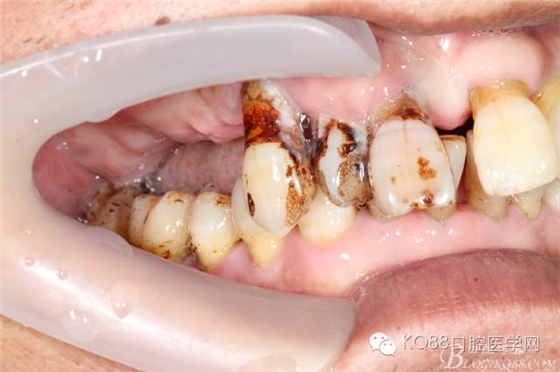

檢查:11、12、13Ⅲ度松動,牙齦退縮,根面暴露,14、15、16、17缺失,余牙不同程度牙齦退縮。

診斷:牙列缺損 牙周炎